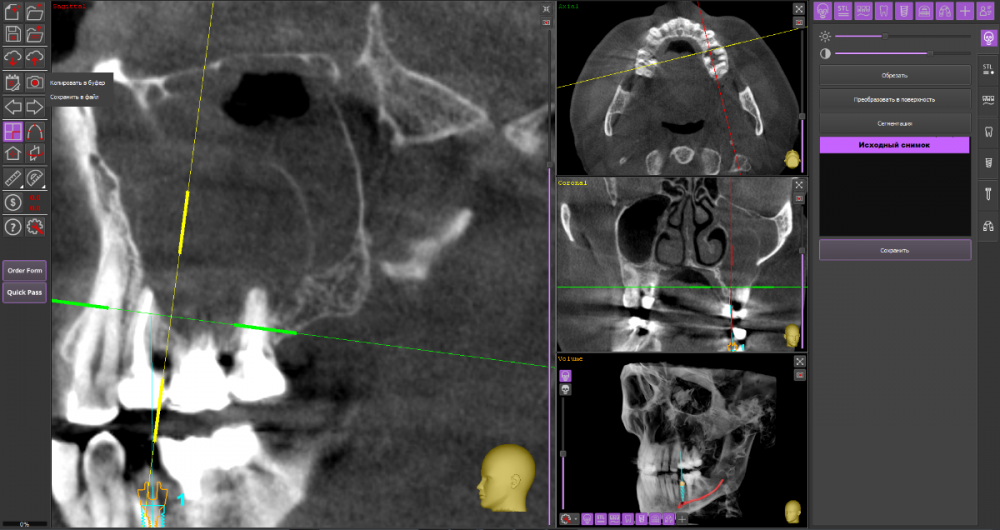

wladdX Опубликовано 22 марта, 2021 Поделиться Опубликовано 22 марта, 2021 При изучении КЛКТ, сделанной по другому поводу, обнаружил радикулярную кисту с врастанием в в/чел синус, размерами около 3*3*3см. Костных стенок кроме нижней и медиальной уже нет. Скрытый текст Как к этому делу подступиться правильно? Ссылка на комментарий

wladdX Опубликовано 24 марта, 2021 Автор Поделиться Опубликовано 24 марта, 2021 (изменено) Найдены старые КТ, посмотрел: виновники 26 и 27 в равных долях. 25 включен позже, к\каналы у него обтурированы хорошо, прослеживаются остатки периодонта, при операции посмотрю на него из полости кисты Изменено 24 марта, 2021 пользователем wladdX Ссылка на комментарий